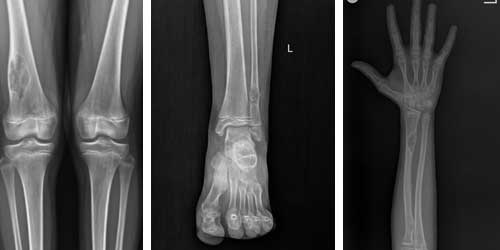

Osteochondrom: Es ist einer der häufigsten gutartigen Tumoren und tritt normalerweise in wachsenden Knochen auf.

Enchondrom: Es handelt sich um einen Tumor, der vom Knorpelgewebe ausgeht und in den Hand- und Fußknochen vorkommt.

Osteoid-Osteom: Es handelt sich um einen kleinen Tumor, der meist in den langen Knochen auftritt und Schmerzen verursacht.

Osteosarkom: Es ist die häufigste Art von bösartigem Knochenkrebs und tritt meist in den Beinknochen auf.

Mithilfe von Verfahren wie Röntgen, Magnetresonanztomographie und Computertomographie können Lage und Größe des Tumors bestimmt werden. Die Untersuchung einer Gewebeprobe des Tumors im Labor ist ein entscheidender Schritt, um festzustellen, ob der Tumor gut- oder bösartig ist. Bestimmte Marker können auf das Vorhandensein von Knochenkrebs hinweisen.